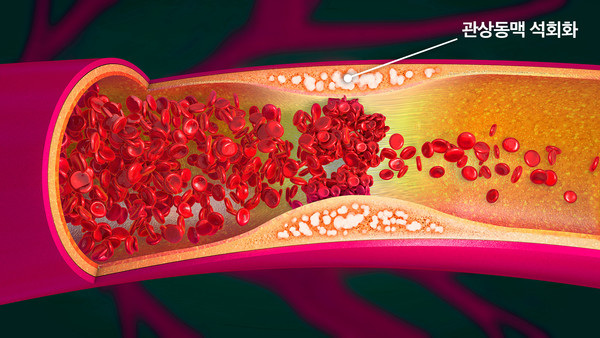

관상동맥 석회화는 관상동맥의 벽에 칼슘이 축적되는 상태를 말합니다. 이 과정은 일반적으로 노화와 관련이 있으며, 심혈관계 질환의 지표로 잘 알려져 있습니다. 관상동맥은 심장에 혈액을 공급하는 주요 혈관으로, 이곳에 석회화가 발생하면 혈액의 흐름이 방해받고 심장으로 가는 산소와 영양소의 수급에 어려움을 초래할 수 있습니다. 이 상태는 종종 무증상이기 때문에, 발견되었을 때 이미 심각한 문제로 발전해 있을 가능성이 높습니다.

동맥경화증은 관상동맥 석회화와 밀접한 관계가 있습니다. 동맥경화가 진행되면 혈관 내벽에 지방덩어리와 염증 세포가 축적되고, 이곳에 칼슘이 쌓이게 됩니다. 이러한 과정은 시간이 지남에 따라 점차 진행되며, 이를 통해 관상동맥의 유연성이 떨어지고 혈액의 흐름이 저해됩니다. 결과적으로, 협심증이나 심근경색과 같은 중대한 심장 질환으로 이어질 수 있습니다.